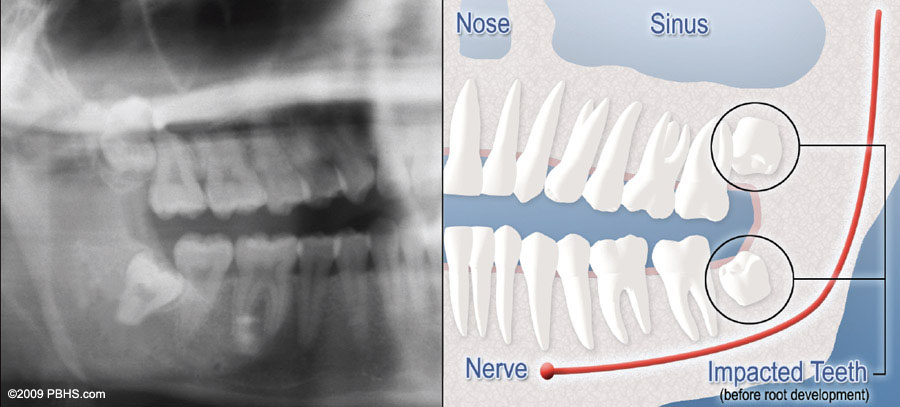

wisdom tooth soft tissue impaction

Complete Bony Impaction

There is NO space for the tooth to erupt. It remains embedded in the jaw bone or if even partially visible requires complex surgical techniques for removal. The impacted wisdom tooth may also be in an unusual position and difficult to remove. This situation can also arise when the shape or size of the jaw bone and other facial structures make removal of this tooth significantly more complex.